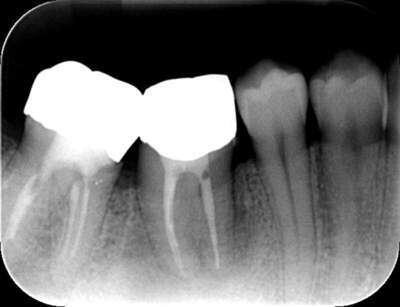

2021.4.3 定期検診時

この時はまだ症状がなかった

しかし歯は縦に割れており、いつ痛みが出てもおかしくないような状態であることは説明していた。

2022.1.15 根尖性歯周炎の急性化

疼痛ありで急患来院。

前々から爆弾抱えているような物で、何かあったら抜歯と伝えていた部位。以前よりクラウンマージン下で歯根縦破折であったが、症状なしで経過観察をおこなっていた。

2022.7.9 経過観察後

口腔内写真

レントゲン写真

根管治療後3ヶ月です。根のまわりの骨がやや白くなってきているのがわかります。だんだん骨の添加がみられている証拠になります。

ここまで治癒していればかぶせ物をかぶせても問題ないと判断しました。